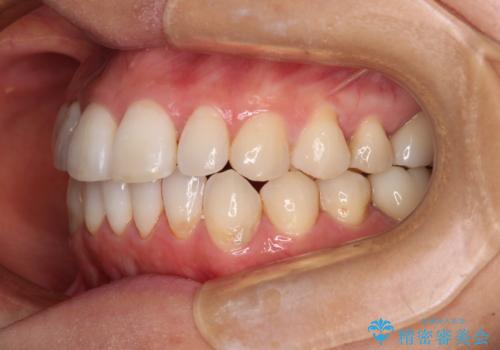

- 捻れた前歯と目立つ銀歯を気にして来院された患者様です。

歯列不正は軽微であったため、インビザライン・ライトにて改善することとしました。

左下大臼歯は根管治療が必要であったため、矯正治療前に根管治療を行い、その後矯正治療を行うこととしました。

矯正治療後には期にある銀歯を全てセラミッククラウンなどで補綴治療することとしました。

インビザライン・ライトによる矯正治療であったので、時間をかけずに治療を終えることができました。

口を開ける度に目立っていた銀歯もセラミックで自然な口元の印象となりました。